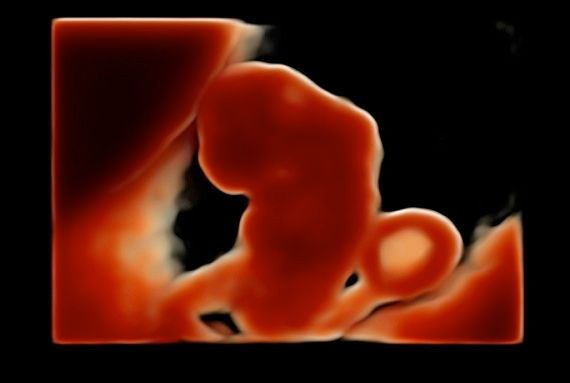

Subito dopo la laurea, il dottor Tommaso Incandela, ha conseguito l'idoneità ospedaliera nella branca di Ostetricia e Ginecologia con il giudizio finale di ottimo. Dall'Aprile 1977 fino al Gennaio 1982, su delibera del consiglio di facoltà, ha svolto la funzione di medico interno della seconda cattedra di Ostetricia e Ginecologia con mansioni didattiche, di assistenza e di cura. Dal Luglio 1981 al mese di Ottobre 1992 ha ricoperto la funzione di assistente di ruolo presso la seconda divisione di Ostetricia e Ginecologia dell'Ospedale Civico e Benfratelli di Palermo. Dal 1 Novembre 1992 fino alla fine di Giugno 1998 è stato dirigente medico del Consultorio familiare di Santa Flavia. Dal Luglio 1998 a tutt'oggi si dedica a tempo pieno all'attività libero professionale occupandosi di ecografia ostetrica e ginecologica con particolare riguardo per la diagnosi prenatale di patologie cromosomiche e malfomative (studio di aneuploidie cromosomiche su DNA fetale prelevato dal sangue materno, amniocentesi precoce, ecocardiografia fetale, ecografia morfologica e cardiotocografia) tutte queste indagini sono inserite nel monitoraggio della gravidanza. Il dottor Tommaso Incandela si occupa altresì di diagnosi precoce e terapia di patologie del tratto genitale inferiore e nel corso degli anni ha acquisito una notevolissima esperienza nell'ambito della terapia conservativa dei fibromi uterini mediante terapia farmacologica e/o inserimento di spirali medicate al progestinico. Da un punto di vista chirurgico il dottor Incandela si occupa di patologie del corpo uterino ivi compresa l'asportazione di fibromi con conservazione dell'utero stesso anche in pazienti meno giovani e con assenza di desiderio di prole. Il dottor Incandela si occupa anche di chirurgia del pavimento pelvico con particolare riguardo per la terapia dell'incontinenza urinaria, dei prolassi uterini e vescicali e delle lacerazioni antiche da parti pregressi.

• Ecocardiografia fetale

• Ecografia morfologica